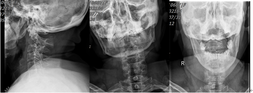

• 突破手術(shù)“禁區(qū)”成功實施頸寰樞椎內(nèi)固定手術(shù)

68歲的朱大媽騎電動車外出,不慎摔倒傷及頭頸部,求診漳州市中醫(yī)院骨傷科,行頸椎X線、CT、MRI檢查結(jié)果為:齒狀突骨折伴寰樞椎脫位。該部位的骨折伴脫位對于任何年齡段的患者都是非常危險的,手術(shù)難度和風(fēng)險非常高。寰樞椎釘棒內(nèi)固定融合術(shù)是治療此類疾病的最佳方案之一,但對手術(shù)團(tuán)隊醫(yī)護(hù)人員的要求極高。        圖一:頸椎齒狀突骨折、骨折移位伴寰樞椎脫位      圖二:頸椎齒狀突骨折,骨折線前下往后上,屬于IIC型    寰樞椎在人體結(jié)構(gòu)中占有極為...